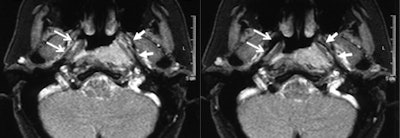

Real-time imaging showed regular opening of the right eustachian tube during Valsalva maneuver (open arrows, right image: neutral position; left image: Valsalva maneuver). The left tube opens only in the anterior part but not in the middle part, due to compression from the tumor (arrows).Krombach was based at University Hospital, University of Technology (RWTH) in Aachen, Germany when she conducted the head and neck study, along with radiologists Anna Luekens and Dr. Rolf Guenther from RWTH and Dr. Ercole DiMartino from the department of otolaryngology and head and neck surgery at DIAKO Ev. Diakonie-Krankenhaus in Bremen, Germany. The group's work was published online first by European Radiology on 13 October.